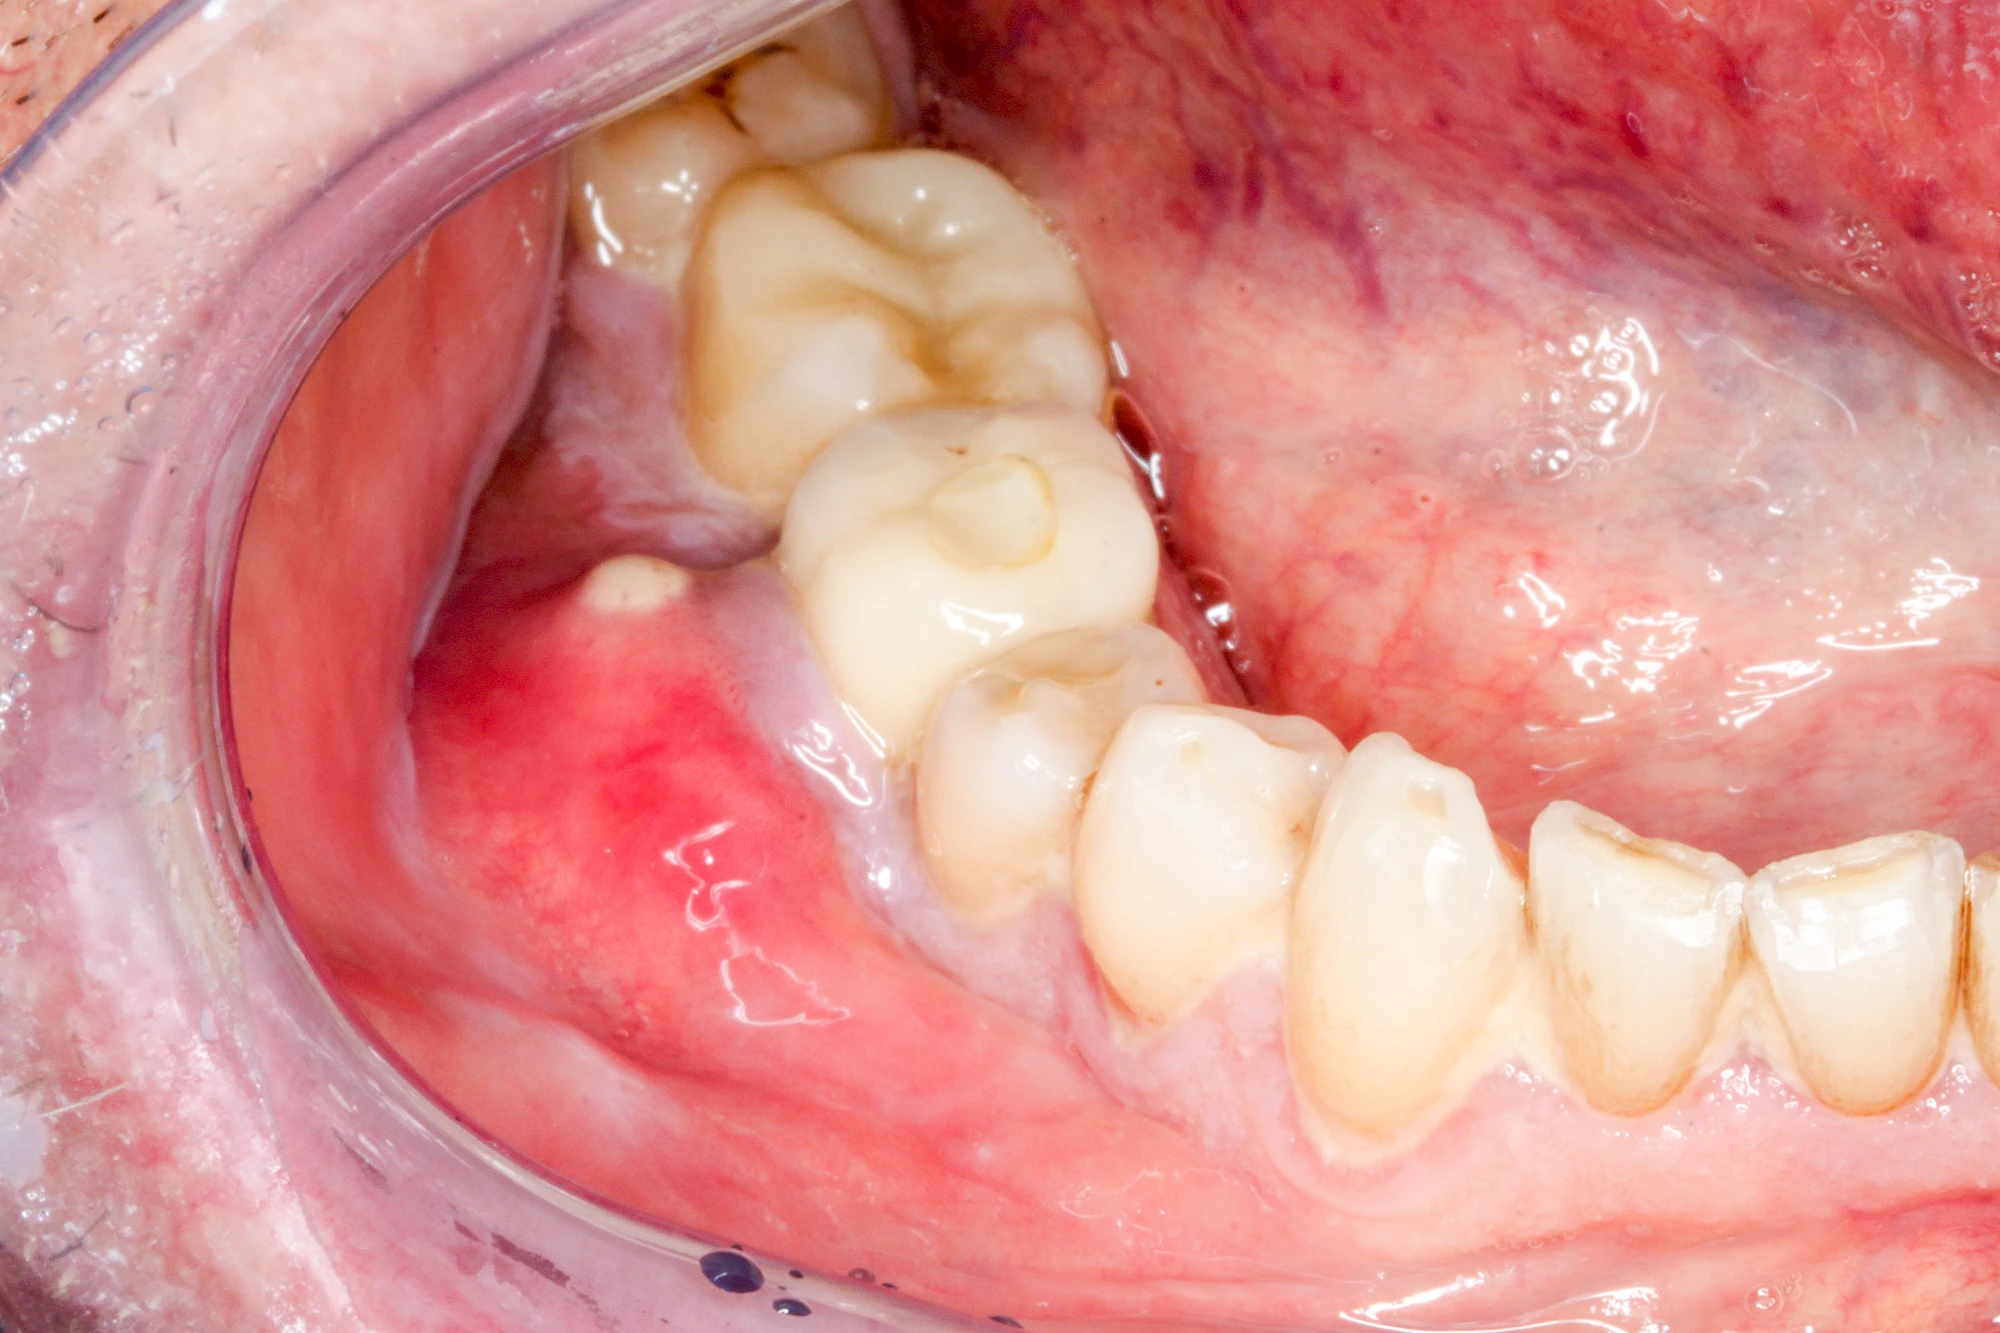

Diese Vermehrung von Bindegewebe in einem frei gewordenen Raum ist eine Sonderform der Anpassungsreaktion menschlicher Zellen und wird als Vakatwucherung bezeichnet.

Früher wurden im Unterkiefer mitunter Brücken zum Ersatz fehlender Zähne als sogenannte "Schwebebrücken" gestaltet. Die Idee dabei war, dass man die Brücke insgesamt besser reinigen kann. Allerdings war das für die Patienten mitunter irritierend für die Zunge und vor allem beim Essen gewöhnungsbedürftig. Teilweise haben sich hier reaktiv Vakatwucherungen der Kieferkammschleimhaut gebildet und den Raum unter der Brücke wieder verschlossen.